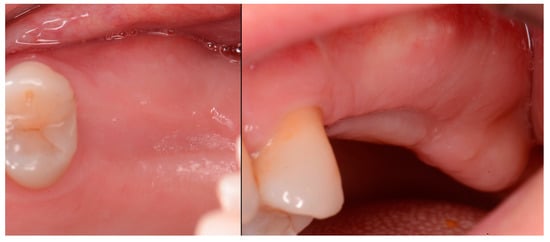

The patient returned at 10 weeks post-2nd-implant placement and a screw-retained restoration was placed on the 1st molar and a radiograph was obtained (Figure 13, left). Impressions were obtained and the restoration on the 2nd molar was placed at a subsequent appointment. Soft tissue was healthy at placement of the restoration on the 2nd molar and no marginal inflammation was noted at either site (Figure 14, left). Soft tissue at the 1-year recall remained healthy and lacking in inflammation (Figure 14, middle). At a 2-year recall, a radiograph was obtained and bone was noted to be stable at both implants (Figure 13, right). Soft tissue at the 2-year recall remained stable and no change in marginal position was noted compared to initial restoration placement (Figure 14, right).

Figure 13.

Radiograph at 10 weeks implant integration at the 2nd molar (left) and two years following restoration of the implant at the 2nd molar showing the improved vertical regeneration between the implants (right).

Figure 14.

Soft tissue at placement of the restoration on the 2nd molar (left), at 1 year post-restoration (middle) and at 2 years post-restoration (right) demonstrating maintenance of the keratinized tissue long term.